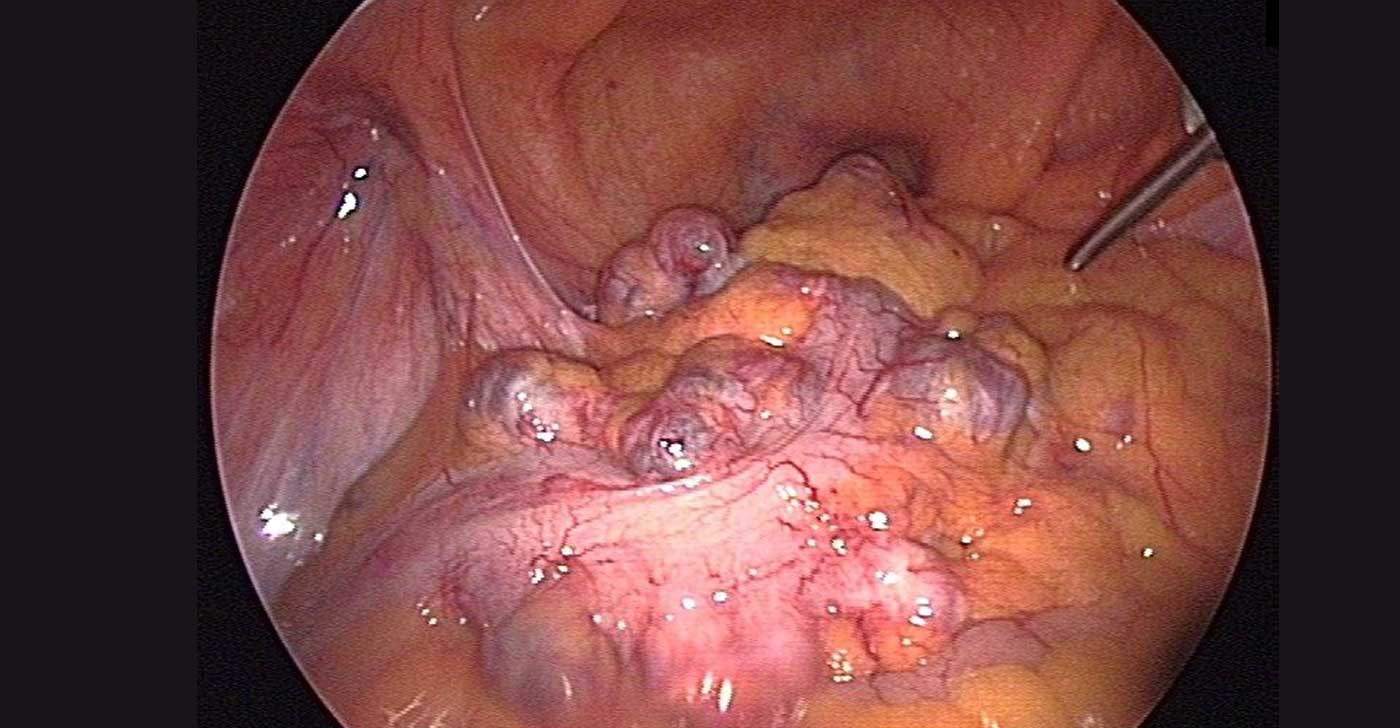

Laparoscopic view inside abdomen during colon cancer surgery

Colon Cancer

Laparoscopic Colon Cancer Surgery

Keyhole removal of the affected section of the colon — including right hemicolectomy, left hemicolectomy, and total colectomy. The magnified camera view allows precise dissection around blood vessels and lymph nodes.